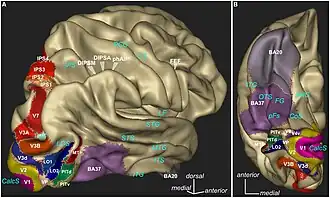

La corteza visual, está conformada por el área estriada, llamada visual primaria (V1) y por las áreas visuales corticales extra-estriadas, nombradas como V2, V3, V4, y V5.

Cada lóbulo occipital, se divide en varias áreas de función visual.

La región peri-estriada del lóbulo occipital está involucrada en el procesamiento visual espacial, la discriminación del movimiento y la discriminación del color.[14]